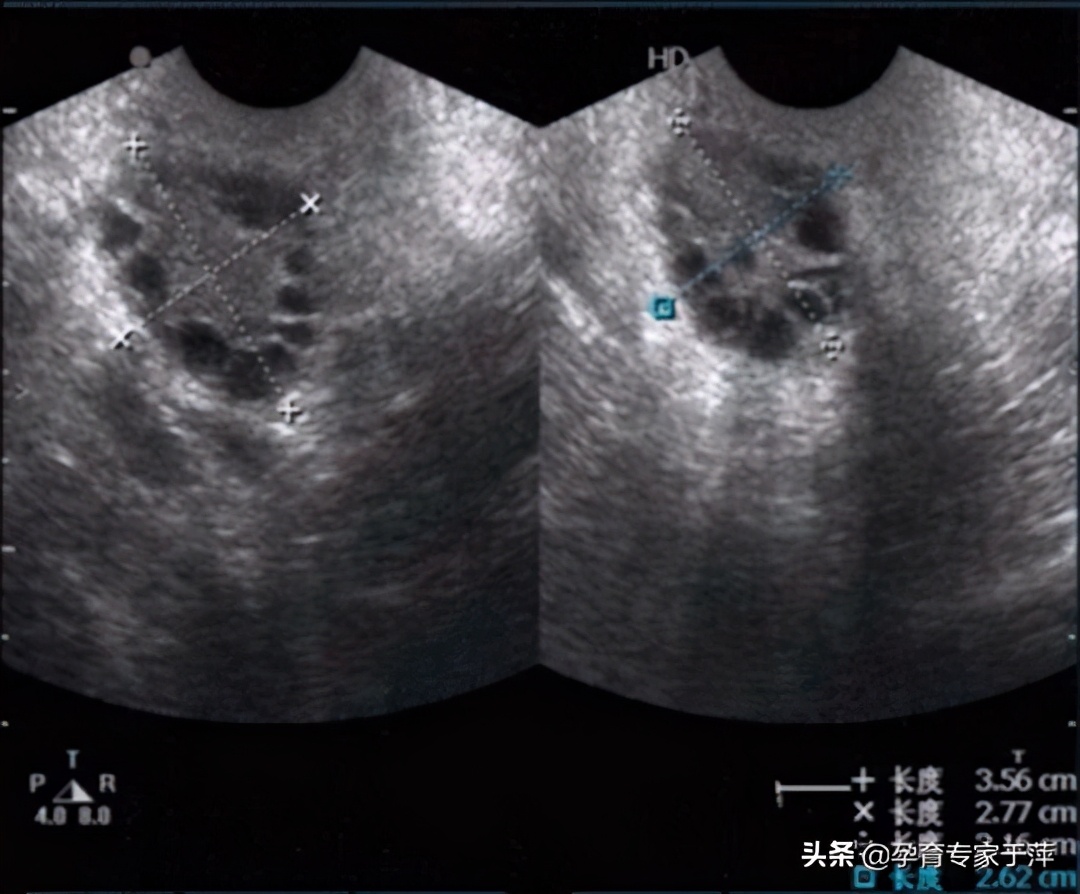

3、卵巢多囊样改变(医生指导下行子宫附件彩超发现)。